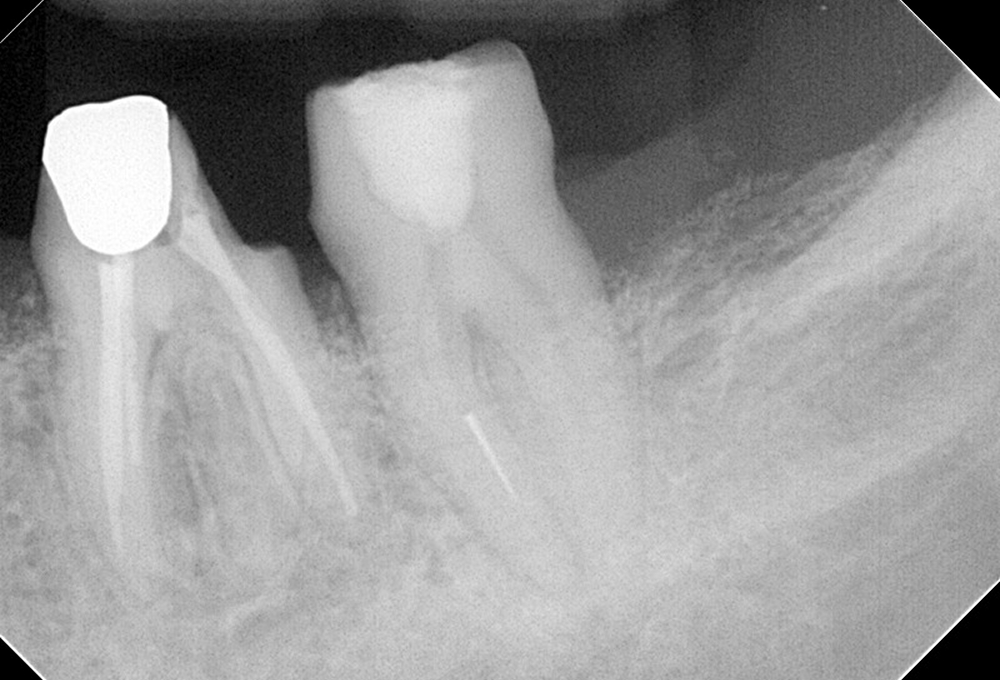

①術前 下顎大臼歯近心根破折ファイル有

③破折ファイル除去後